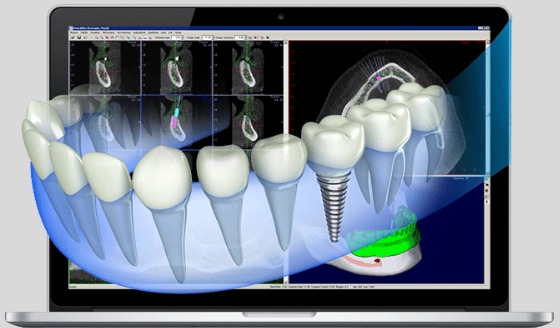

Implantodontia

Precisão milimétrica com planejamento 3D.

No COES, a tecnologia, conforto e resultados são parte essencial do cuidado. Nosso fluxo de trabalho, totalmente digital, integra a tecnologia CAD/CAM, Chairside, através do uso de Scanner Intraoral, Software de Planejamento, Impressora 3D, Fresadora e Tomografia de Alta Resolução.

Planejamento Digital Completo

Simulações 3D em Tempo Real

Precisão Milimétrica em Cada Procedimento